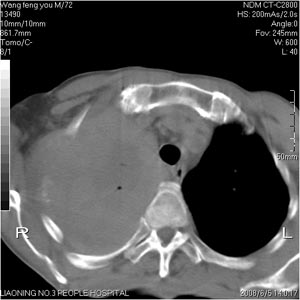

患者:男 72岁 右肩痛半年,近日来咳血,就诊.

可能右肺癌可能性大,肋骨可能有破坏

右侧肺癌并肋骨破坏,右侧胸腔积液。

考虑:右肺上叶中心型肺癌伴肺不张、肋骨转移、肩胛骨转移、右侧胸腔积液。

右肺上叶全叶实变并不张,应为右上叶支气管阻塞所致。7、8层面好象是肋骨破坏。结合临床资料,考虑中央肺癌右上叶阻塞炎病及不张。左肺纤维化灶。右侧胸水。

抽胸水找癌细胞。